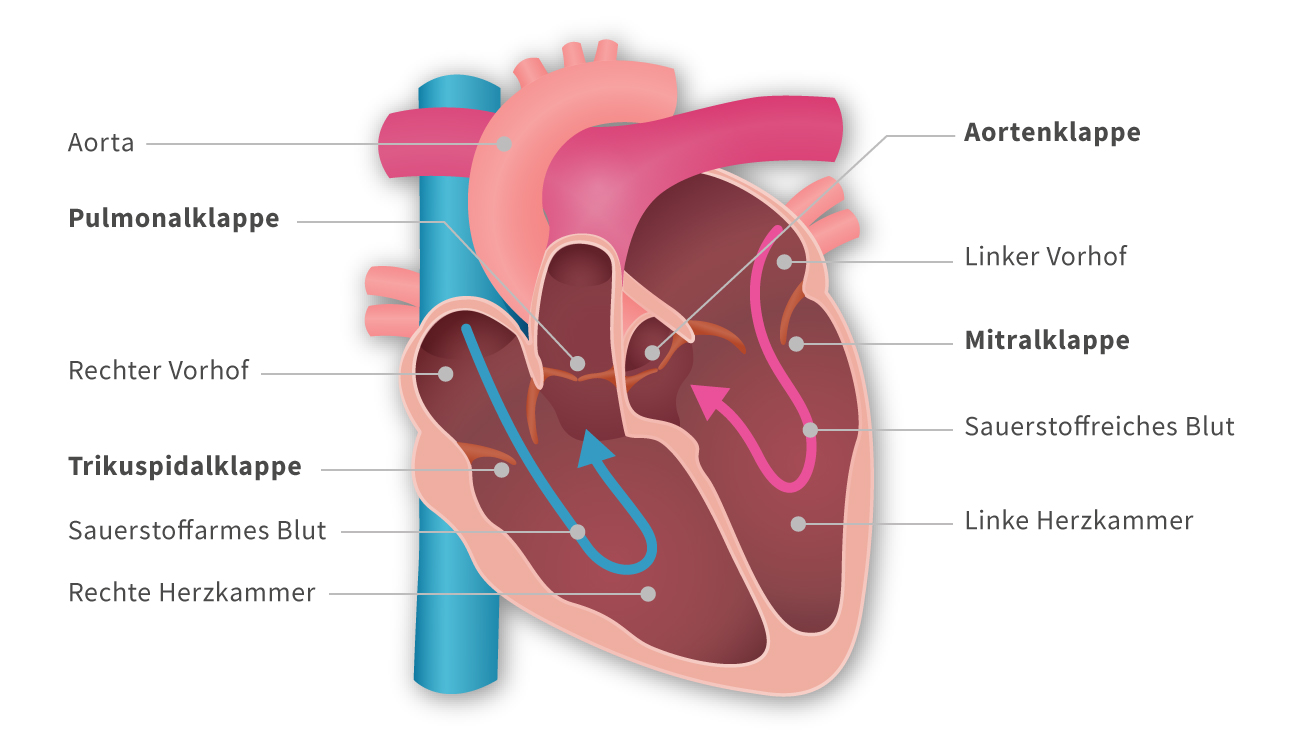

Die Pumpleistung ist die Menge des Blutes, die das Herz innerhalb einer bestimmten Zeit in den Blutkreislauf pumpt. Das gesunde Herz eines erwachsenen Menschen pumpt in Ruhe etwa 5 bis 6 Liter pro Minute. Bei einer körperlichen Belastung steigt dieses Herzminutenvolumen auf 20 bis 25 Liter. Krankheiten können die Pumpleistung des Herzens unnatürlich senken oder steigern.. In jeder Minute wird so einmal die gesamte Blutmenge – beim Erwachsenen fünf bis sechs Liter – durch den Körper befördert. Doch wie schafft das Herz jeden Tag diese Schwerstarbeit und wie funktioniert diese menschliche Pumpe? Herz-Kreislauf-System: So fließt das Blut. Das Herz ist das Zentrum des Blutkreislaufs.

Das Herzzeitvolumen (HZV, englisch cardiac output CO) ist das Volumen des Blutes, das pro Zeitspanne vom Herzen gepumpt wird (Volumenstrom).Die übliche Maßeinheit in der Humanmedizin ist Liter pro Minute, wobei dann vom Herzminutenvolumen (HMV), früher auch Minutenvolumen des Herzens, gesprochen wird.. Das Herzzeitvolumen ist ein Maß für die Pumpleistung des Herzens bezüglich der.. Der venöse Rückstrom zum Herzen bestimmt ganz wesentlich, wie viel Blut das Herz jede Minute auswirft. Abhängig von diesem Rückfluss pumpt das Herz automatisch das zurückströmende Blut in den Körperkreislauf. Je mehr Blut zurückströmt, desto mehr Blut wird vom Herzen ausgeworfen und umgekehrt.